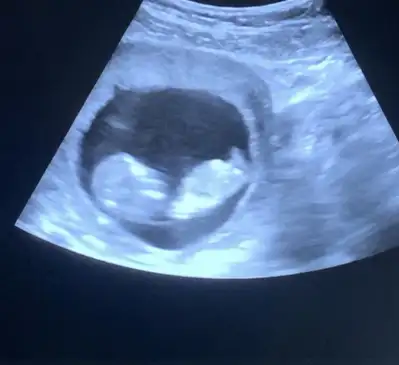

Çok minnoş olduğunu düşünüyorum yerim yaaa hahahKızlar benimki için ne düşünüyorsunuz 12. Hafta bu , ters duruyor Eki Görüntüle 3126437

Çok minnoş olduğunu düşünüyorum yerim yaaa hahahcinsiyeti için kafasını görseydim belki yorumlardım kendimce